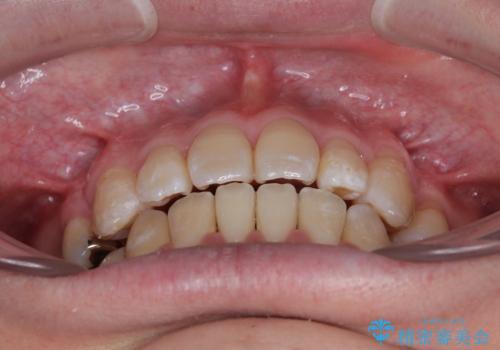

治療期間は約2年。

少しずつ前歯を後ろに下げていくことで、横顔のラインが整い、口元の“出っ張り感”が解消。

治療後には「自然に笑えるようになった」と嬉しいお声をいただきました。